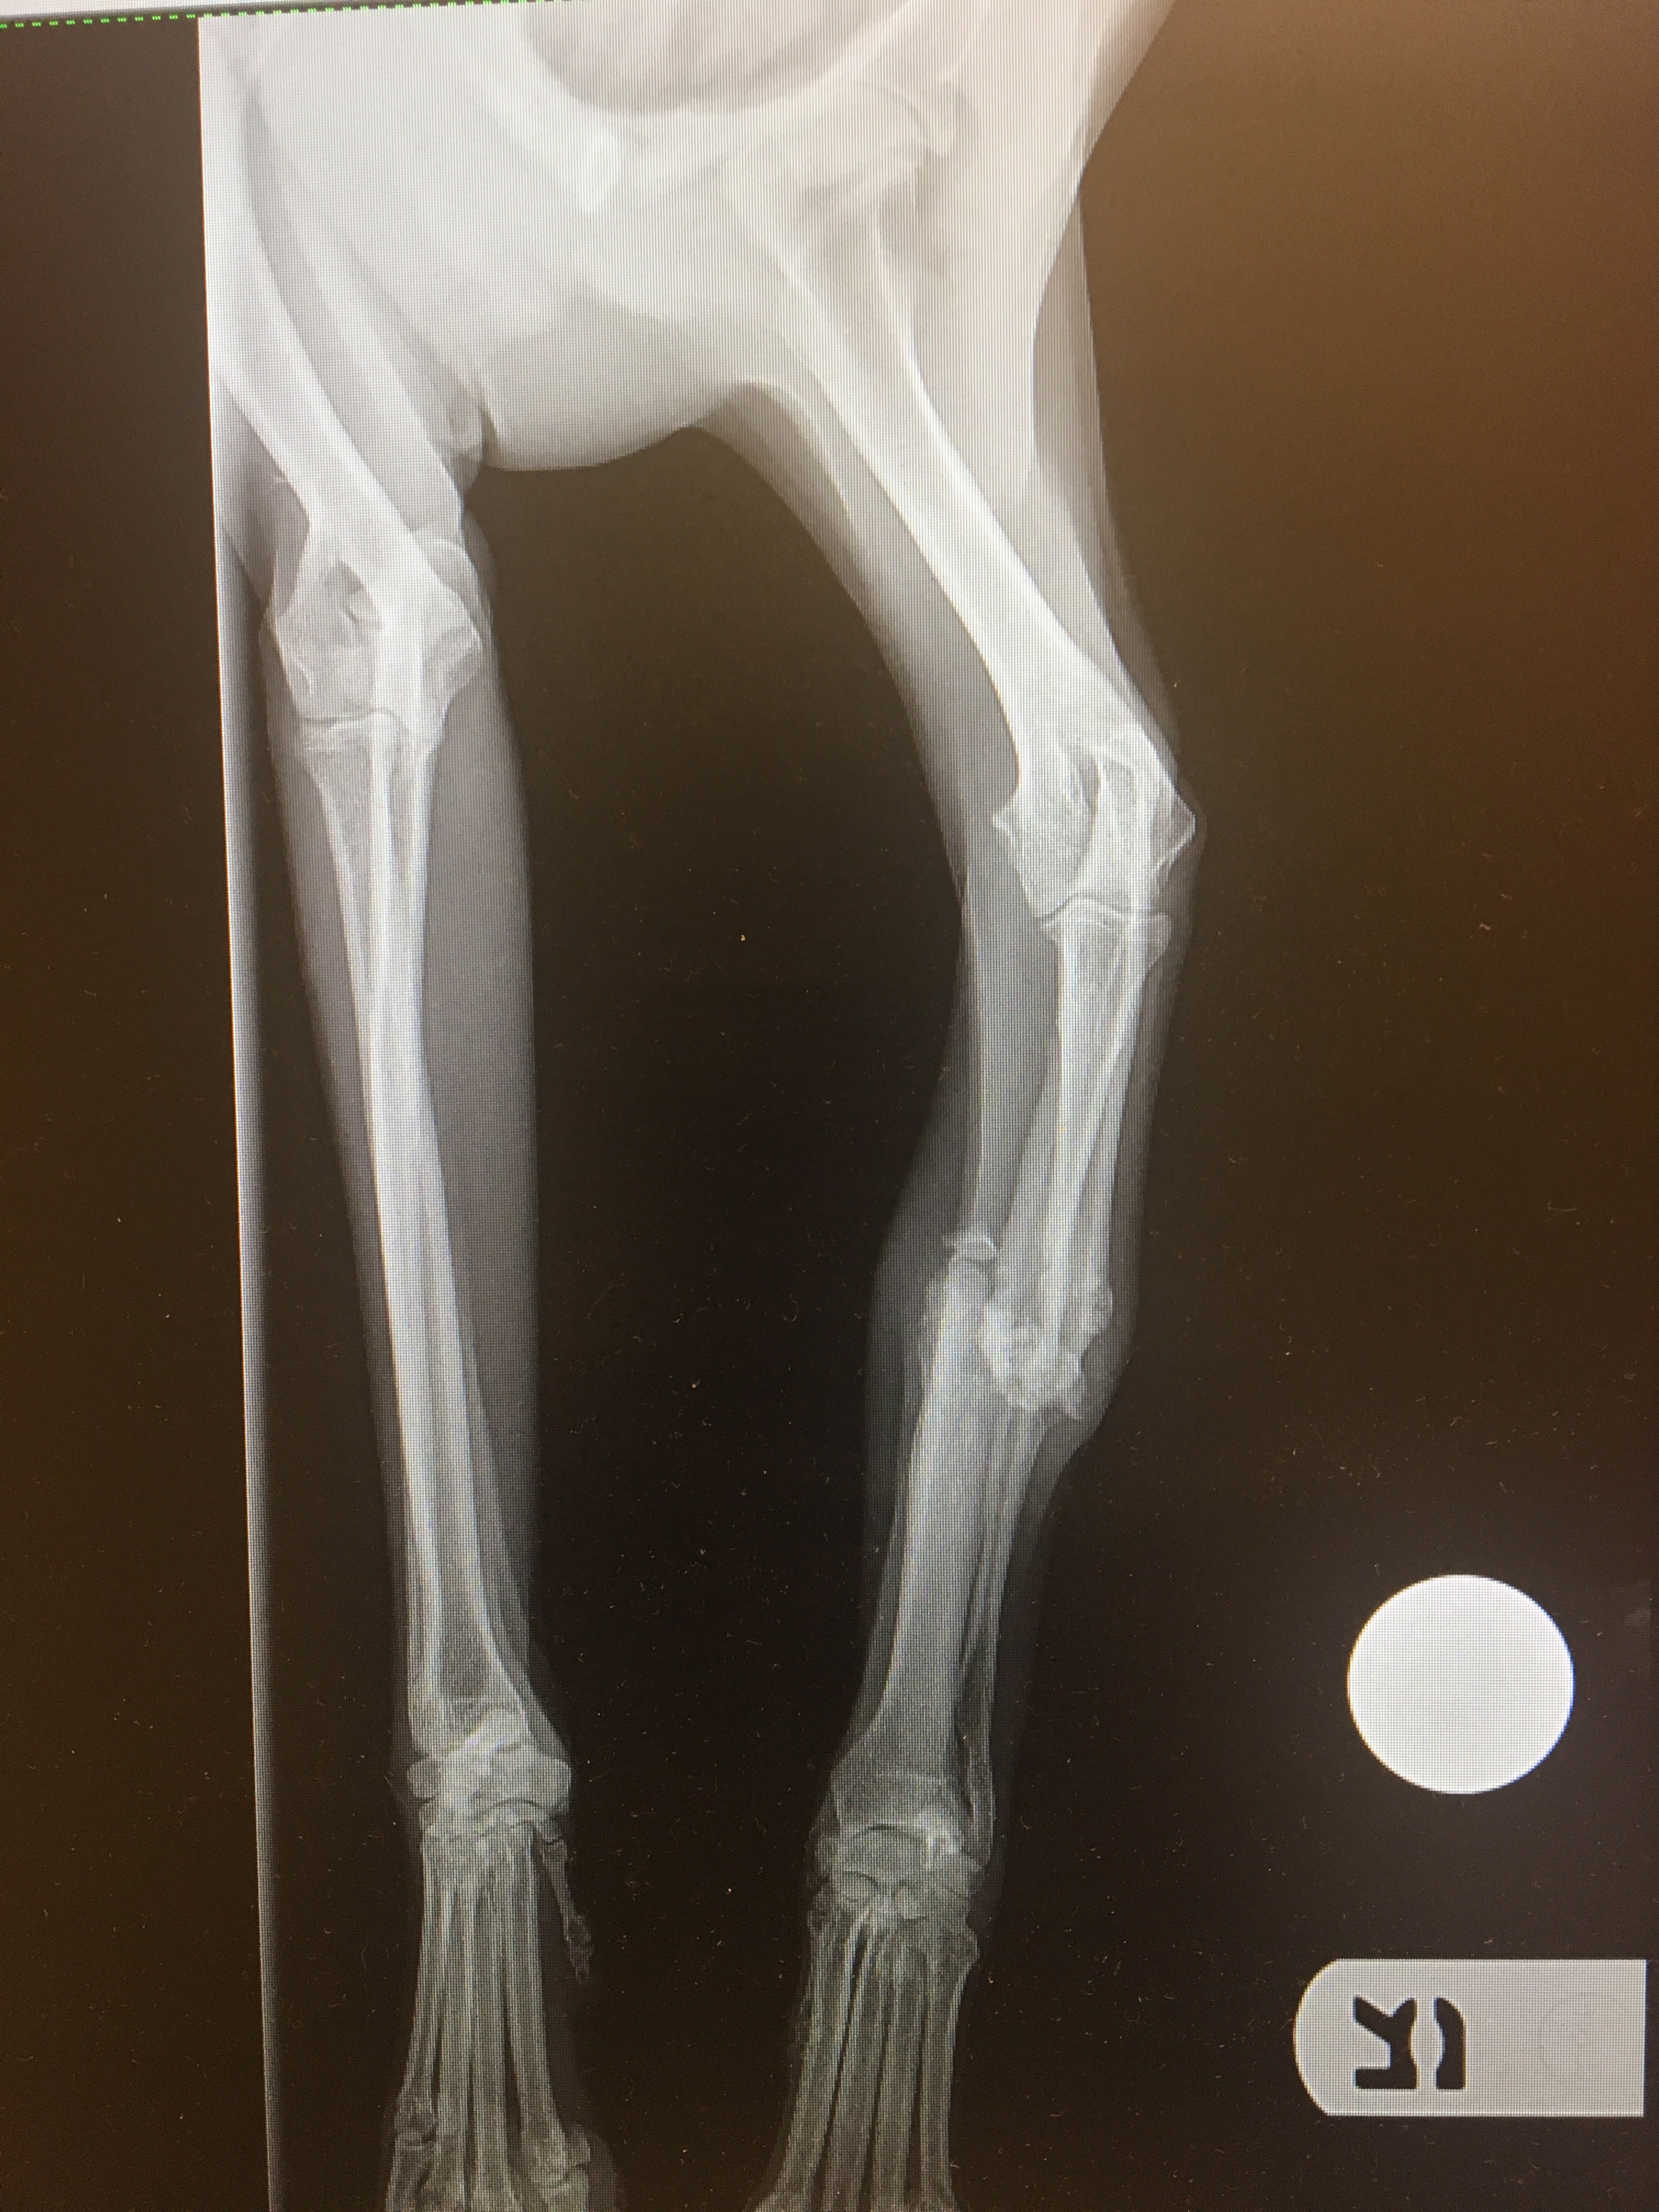

They reported the address to the authorities.  As of yet, nothing has been done to this Breeder.  The ladies that rescued Ralfie began seeing surgeons to see who could fix this poor pups leg.   Money was running low, and sadly the leg was getting worse by the day.  Ralfie has a break in his front leg that is displaced.   His x-rays indicate this is an old injury that Ralfie has been living with for approximately six weeks.

After a thorough examination, Dr. Nanfelt felt like the leg had calcified in a nonunion position which made the leg deformed.  The leg had to go to get rid of the pain Ralfie would always have if the leg remained.  There was no possibility of re-breaking the leg and putting a plate on.   He was not using the leg and was already a tripod so to speak.   We told Dr. Nanfelt to make the final decision during surgery once she saw the damage.  Ralfie would have to have his leg amputated is what she determined.